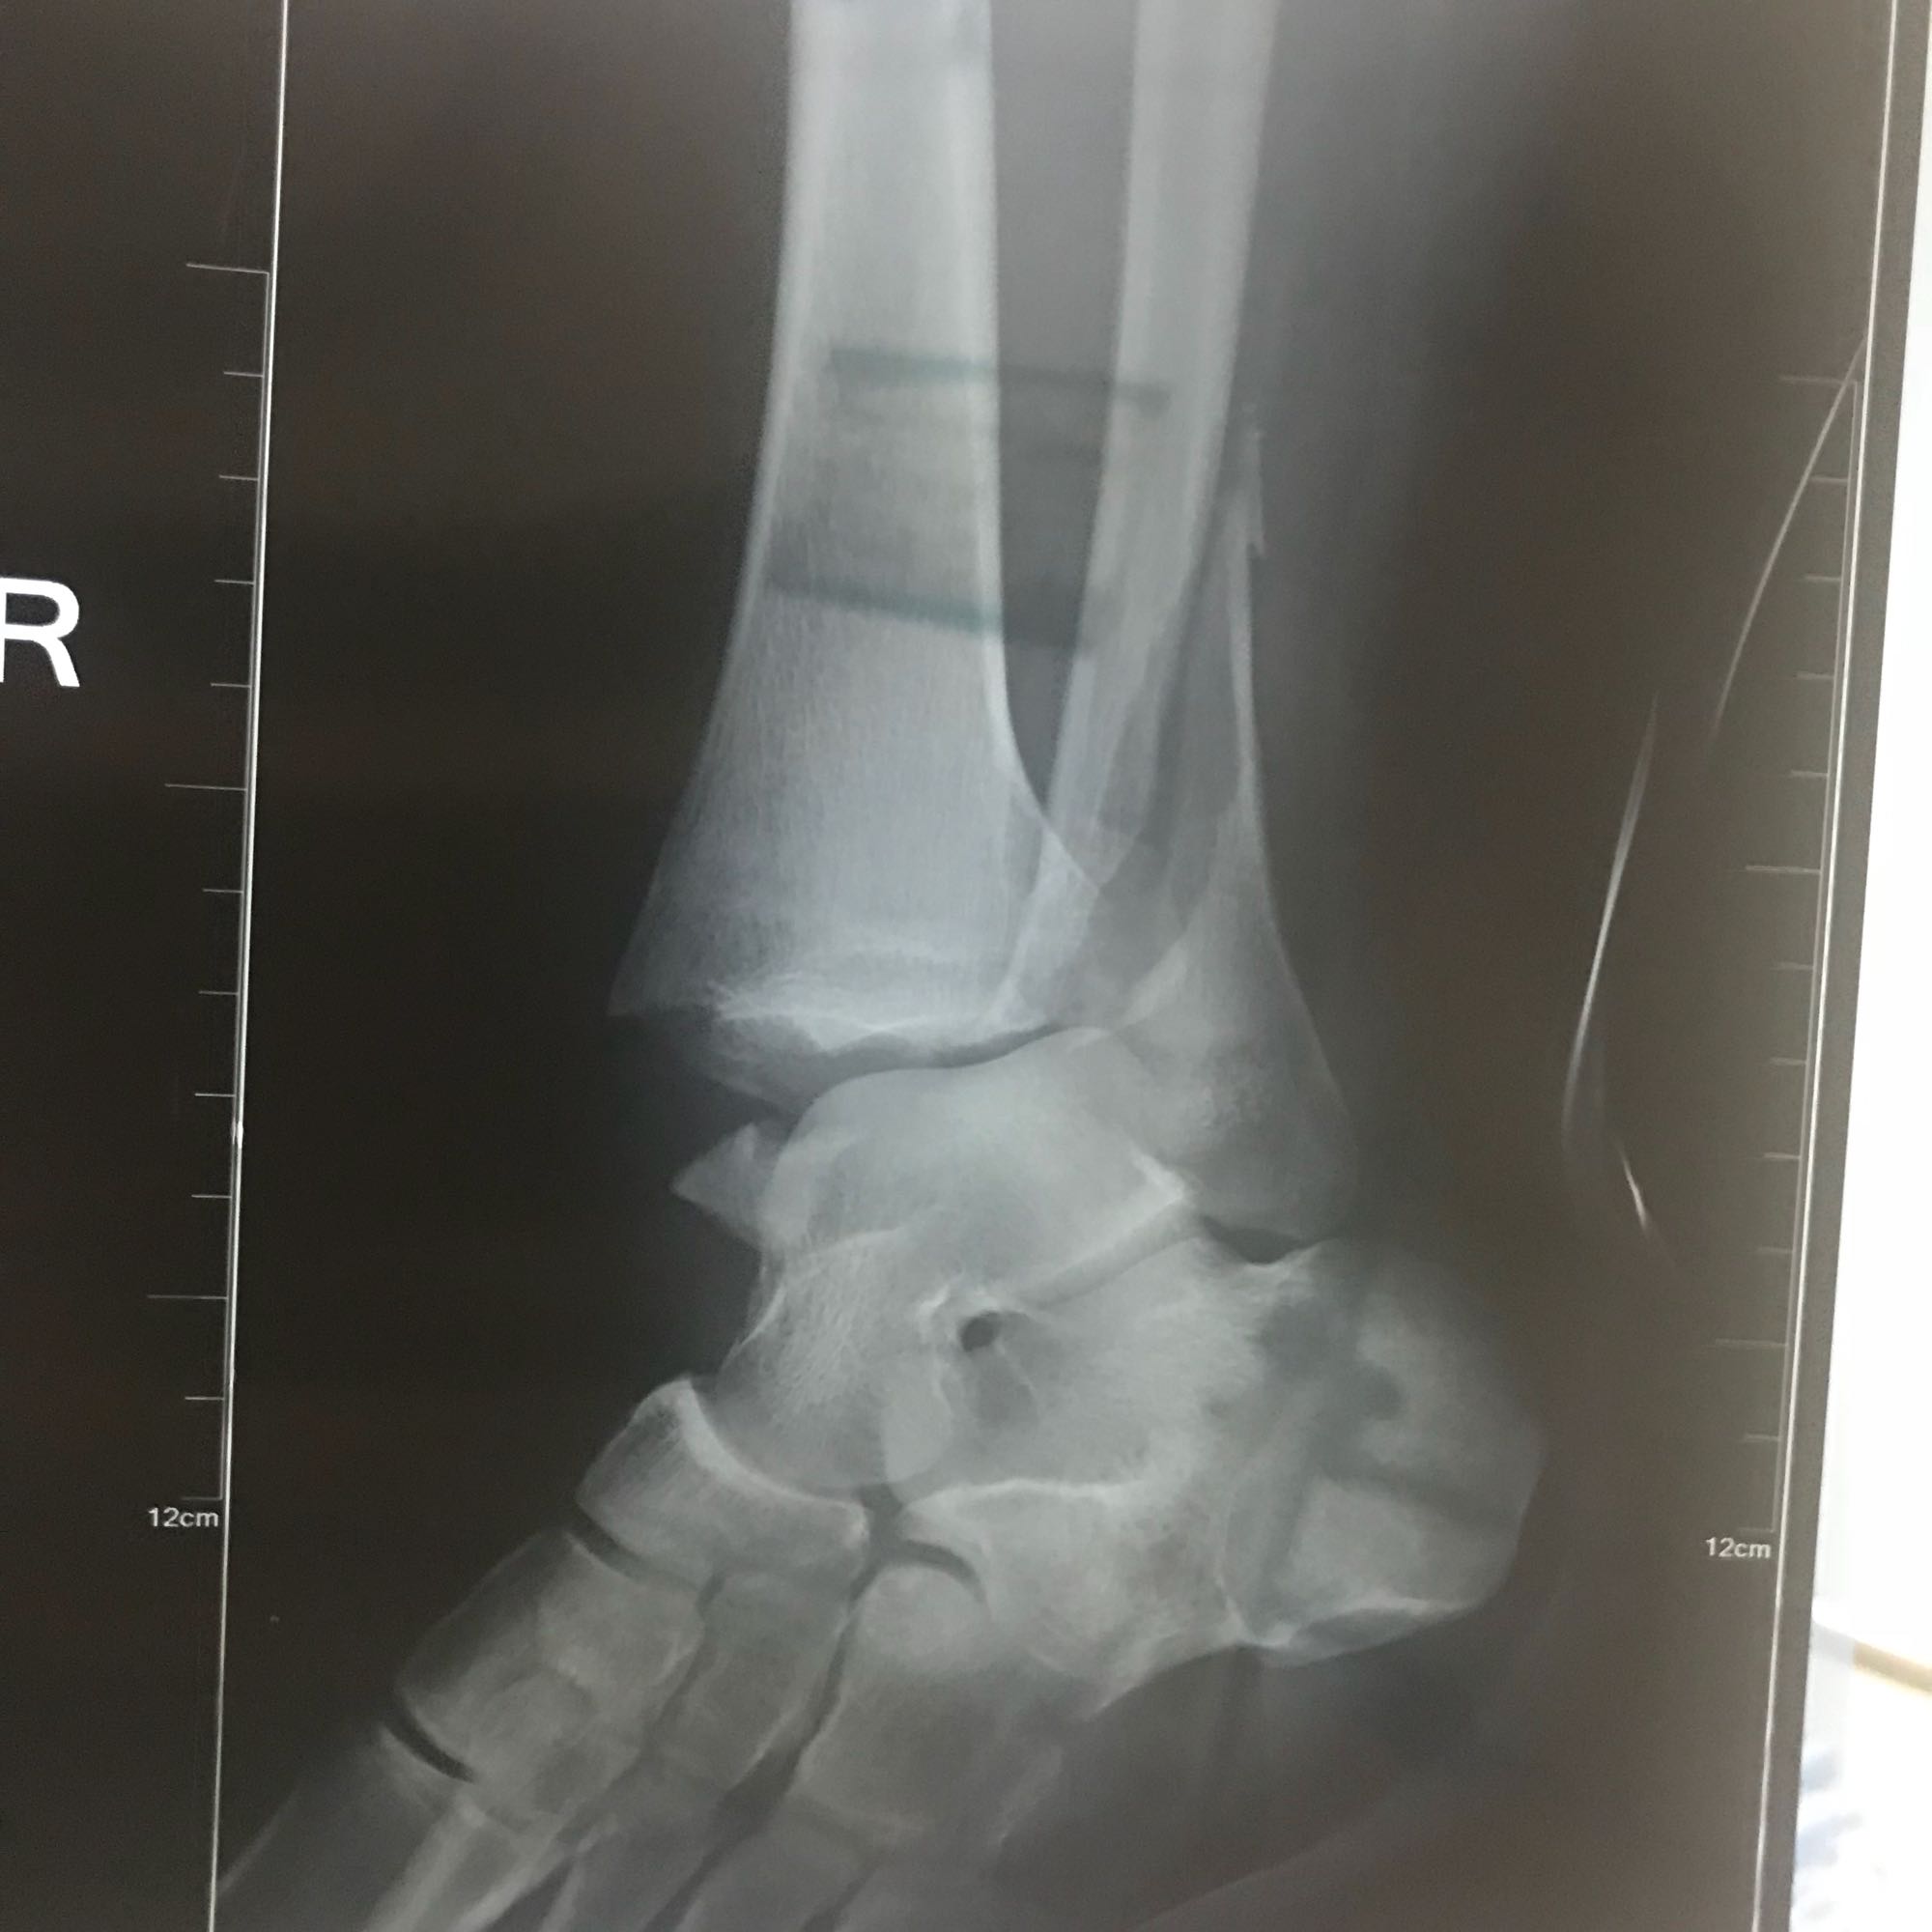

三踝骨折吧

有没有看得来的 我的这个是不是有联合钉,有的话还要取

2018年08月20日 09点08分

没有联合钉咱俩差不多 我是两板12

你这腓骨是两处骨折吗?

2018年09月03日 00点09分

阿波罗太空超人

@乐观的绵羊007

我这是三处 三踝

乐观的绵羊007

对呀,三踝指内外后踝,看你片子腓骨上有两处折痕